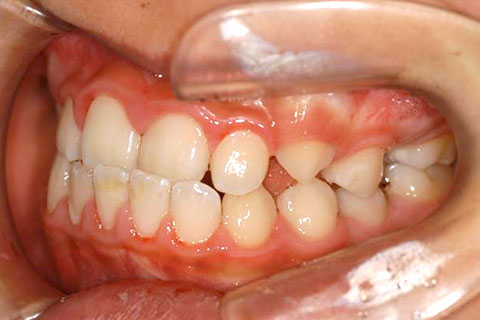

矯正の症例 受け口(反対咬合)

受け口(反対咬合)の症状

下あごが上あごより突出しているか、上あごが下あごより後退している状態で、咬み合わせが逆になっているので反対咬合ともいいます。お子様の場合、受け口(反対咬合)を放置していると、成長期において下あごが過大に成長し悪化しますので、出来る限り早い時期に治療することをおすすめします。受け口(反対咬合)は見た目の問題だけでなく顎の動きを制限し、将来的に顎の痛み(顎関節症)を引き起こす場合があります。また、お子様の場合は、正常な上顎の成長を阻害する可能性があります。